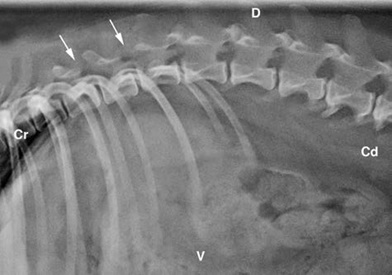

Pug 11 ετών με παραπάρεση και αταξία. Απεικονίζεται απώλεια του φυσιολογικού κυρτού και κοίλου σχήματος των αρθρικών αποφύσεων στην περιοχή από Θ9-Θ12. Τα βέλη δείχνουν την απουσία των οπίσθιων αρθρικών αποφύσεων μεταξύ των σπονδύλων Θ11-Θ12 και Θ12-Θ13.